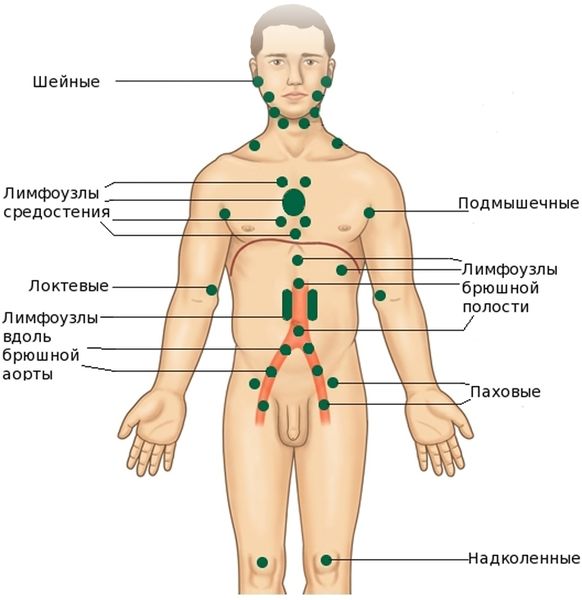

УЗИ лимфоузлов при лимфоме Ходжкина